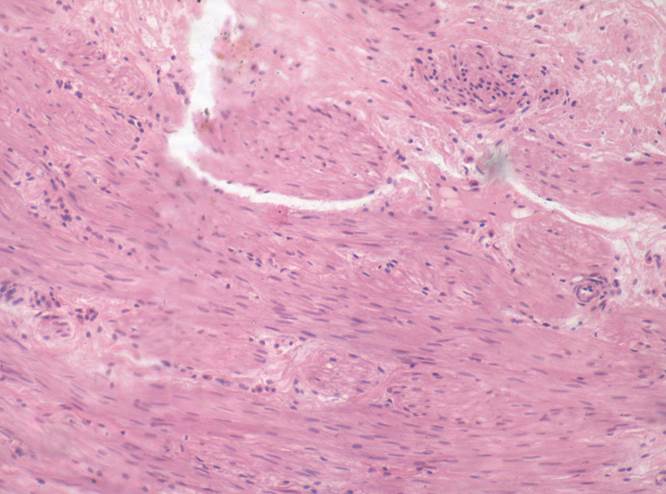

Препарат № 2. «Мочеточник», (окраска гематоксилином и эозином).

Слизистая оболочка:

1. переходный эпителий;

2. собственная пластинка.

II. Подслизистая оболочка.

III. Мышечная оболочка:

3. внутренний слой – продольный;

4. наружный слой – циркулярный.

IY. Адвентициальная оболочка.

5. рыхлая соединительная ткань

6. кровеносные сосуды